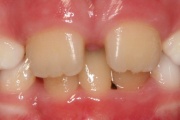

Koonilise kujuga lisahammas ülemiste tsentraalsete lõikehammaste vahel.

Suulaepoolt lõikunud koonilise kujuga lisahammas